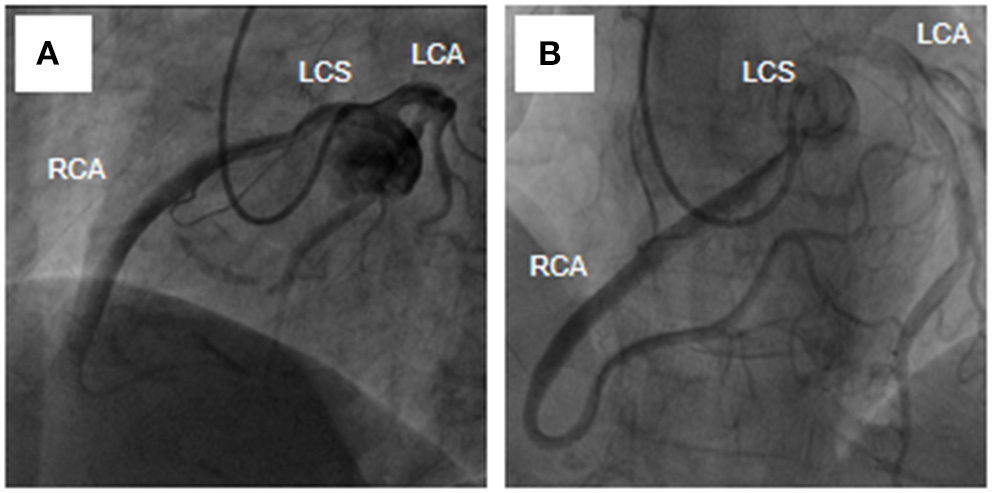

A 54-year-old female was admitted urgently again because of sudden chest and back pain. At her first admission in June 2020, due to chronic atypical chest pain with paroxysmal syncope without any history, she was diagnosed with AAORCA and slight coronary stenosis (Figures 1A,B; Supplementary Video 1) after trans-radial coronary angiography and recovered after 2-week symptomatic treatment with medicine. At this time, no positive signs were found except a blood pressure of 162/90 mmHg at resting conditions and a slight diastolic murmur. An electrocardiogram (ECG) showed the mild ST-segment depression and cardiac troponin I was 0.17 ng/ml. Transthoracic echocardiography showed a Stanford type A aortic dissection (AD) with the widening from the aortic sinus to the thoracic aorta, avulsion injury at the opening of the right coronary artery (RCA), and the RCA originated from the left coronary sinus (LCS) (Figures 2A,B). Total aorta plus coronary CTA clarified the Stanford type A AD involving from the aortic root to the abdominal aorta, while left and right coronary arteries originated from the LCS (Figures 3A–C; Supplementary Video 2). The RCA was abnormally distributed and walked between the aorta-pulmonary artery (Figure 3D; Supplementary Video 3). Considering the risk of dissection rupture and SCD, an emergency surgery of aortic replacement and coronary anomaly correction was performed successfully for the patient. The AAORCA with AAD was identified and the aortic valves and LCS were still normal. We repaired the AAD with ascending aorta and total arch replacement combined with stent-graft elephant trunk technique, and corrected AAORCA with a right coronary artery bypass grafting. Postoperatively, the patient recovered well with medicine therapy including aspirin and clopidogrel, and was discharged on the 9th day after the operation. The patient is well now and has no limitations in daily activities at her 4-month follow-up visit.

Figure 1. Transradia coronary angiography showed AAORCA (A,B). AAORCA, the anomalous aortic origin of the right coronary artery; RCA, right coronary artery; LCS, left coronary sinus; LCA, left coronary artery.